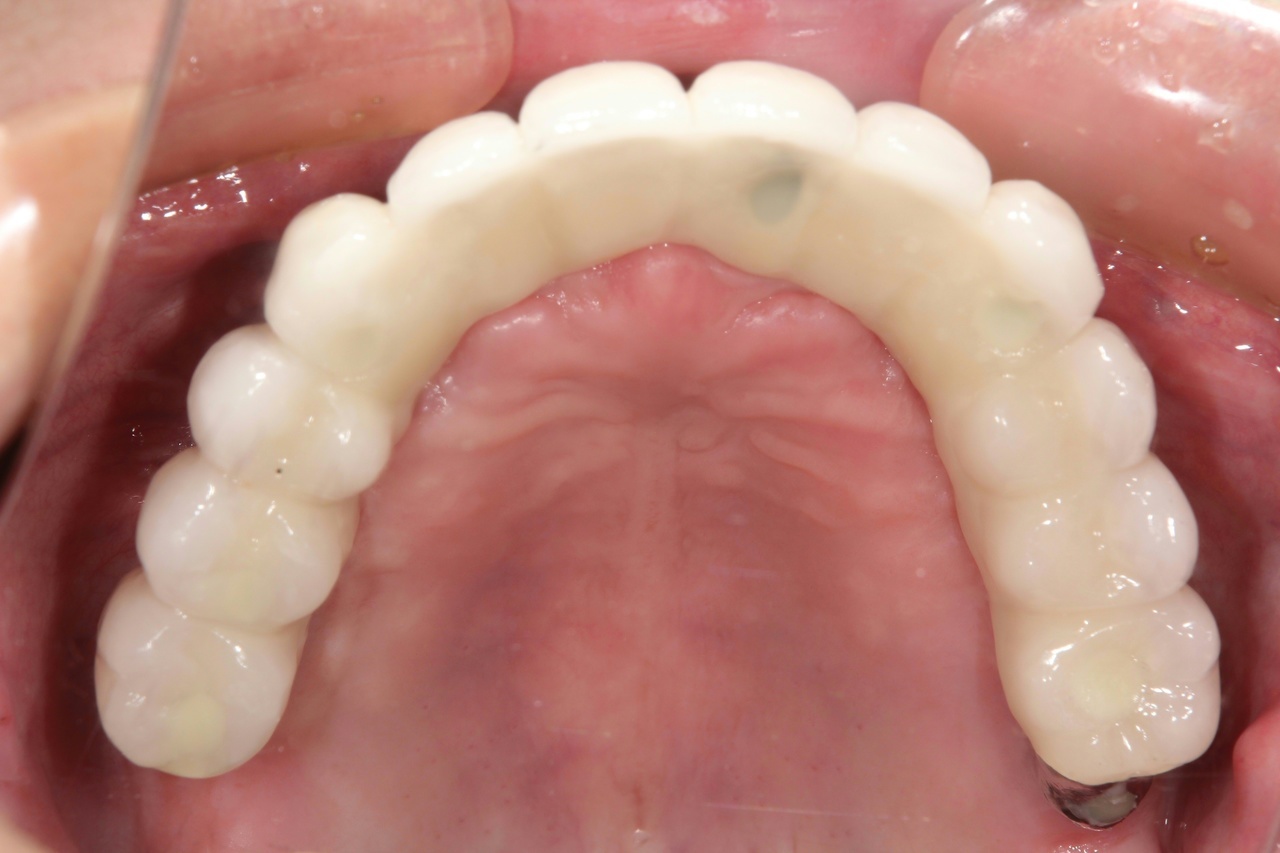

インプラントオーバーデンチャー<ロケータータイプ> (沼津市在住 男性)

インプラントを埋め込み、固定用のロケーターを装着し、入れ歯をしっかりと固定する治療法です。

少ない本数でがっちり噛める治療法です。取り外し可能でしっかり固定できるので、入れ歯の誤飲の心配がなく、手入れがしやすいので寝たきりになっても安心に使用出来ます。

● オーバーデンチャーを外した状態

● オーバーデンチャーを付けた状態

インプラントオーバーデンチャー